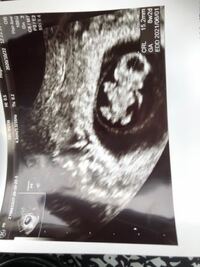

23週6日のエコーです! 性別どちらにみえますか?? 第4子妊娠中で、3人全員女の子なので希望は男の子です👦 ですが元気に生まれてくれたらどちらでも可愛がります!が、、やっぱり気になります😂😂😂 男の子かな?女の子

男の子 女の子 8 週 エコー- 週の男の子のエコー写真 周りの羊水で少し見づらいですが、左側がお尻、右側が足になります。 真ん中にちょこんとシンボルがうつっているのがわかりますでしょうか。 22週の男の子のエコー写真 22周めの男の子の写真です。性別が男の子から女の子に変わった先輩妊婦の体験談 体験談1 妊娠8ヶ月ごろに産婦人科の先生から「男の子で間違いないですよ」言われました。 私も確かにエコーで男の子の象徴をちゃんと見ました。 この子は3人目で、上の子は二人とも女の子だったので

妊娠30週目の女の子のエコー写真 女の子を見分けるのは足の間の突起物が無いかコーヒー豆が見えるか! 女の子の性別判定はいつから可能? 女の子の性別判定はいつから可能なのでしょうか? 男の子も女の子も外性器がしっかりと形成され、 性別判定 男の子か女の子か気になる妊婦さん必見です! エコー検査での見え方の特徴もご紹介します。 性別がわかる時期っていつ?最初はみんな女の子だった。 実は、妊娠7週頃まで見た目はみんな「女の子」なんです。